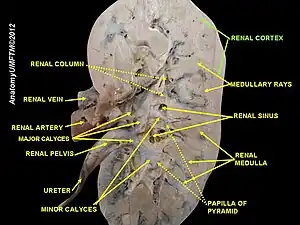

Cortical hypoplasia is a not widely known type of renal hypoplasia where the number of nephron generations is reduced, causing the renal medulla to reduce in size and the renal cortex to decrease in thickness throughout the person's life. This type of hypoplasia is frequently paired with other forms of renal hypoplasia and seems to portray an arrest of nephrogenesis, leading to fewer nephron generations, resulting in smaller renal size in general. The nephrogenesis before the arrest is normal. On the other hand, the medullary rays and renal pyramids have decreased in size with the radial glomerular count reduced to eight or less.[8]